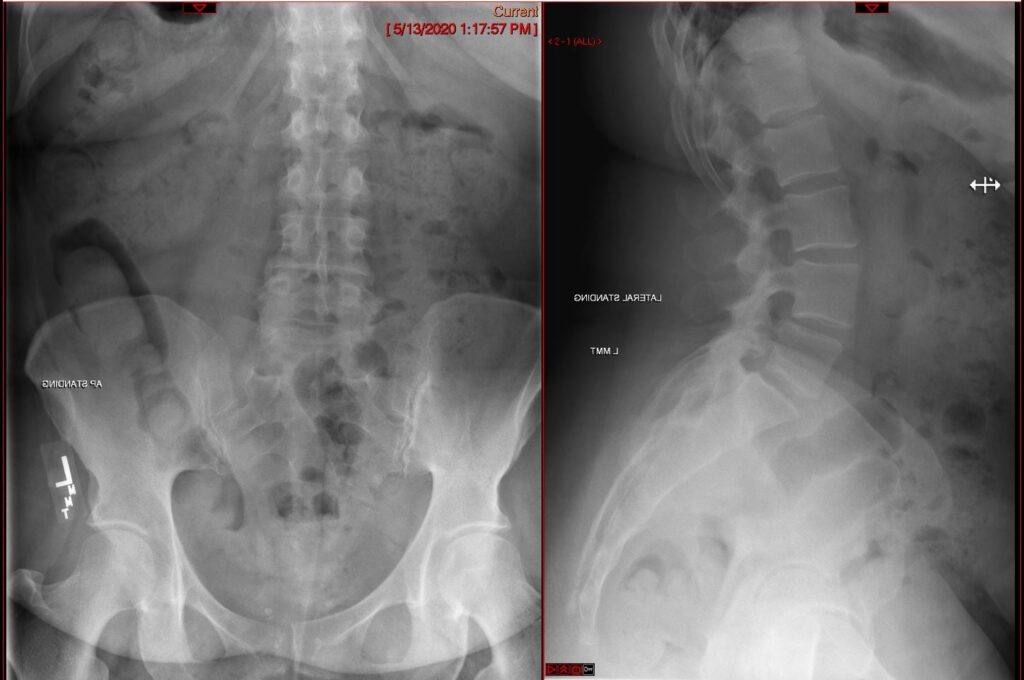

Oblique Lumbar Interbody Fusion